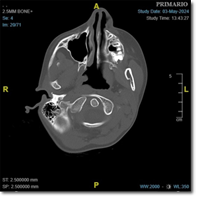

Visitas: 15073

Paciente de 13 años que consulta por una dudosa sensación de disnea. Afebril, sin clínica de...

Brizuela Delgado J, Alquézar Yus P, Vaquero Monje R.

07 octubre 2025